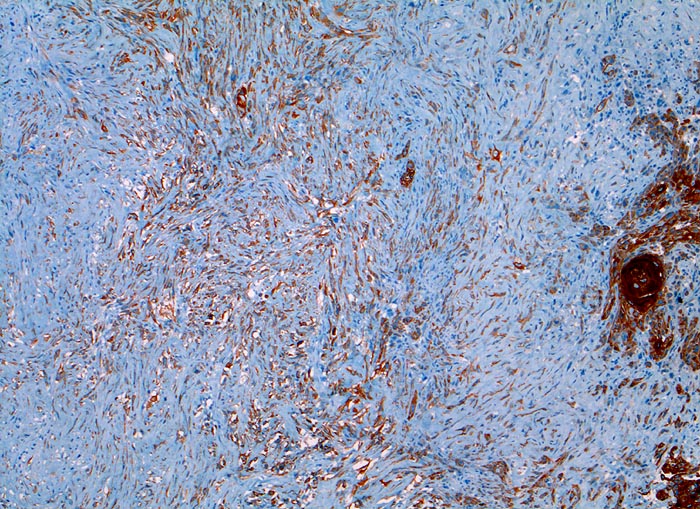

sarkomatoides Plattenepithelkarzinom

Larynx

Der Panzytokeratinmarker Lu-5 färbt sowohl die plattenepithelial differenzierten verhornenden Tumor-Zellstränge rechts im Bild als auch ein Teil der sarkomatoiden entdifferenzierten Tumorkomponente an.

Tumor subglottisch rechts. Immunhistochemische Resultate: CK22, Lu-5, Vimentin positiv

Status nach Larynxkarzinom vor 3 Jahren

Immunhistochemie

Lu5 Panzytokeratin